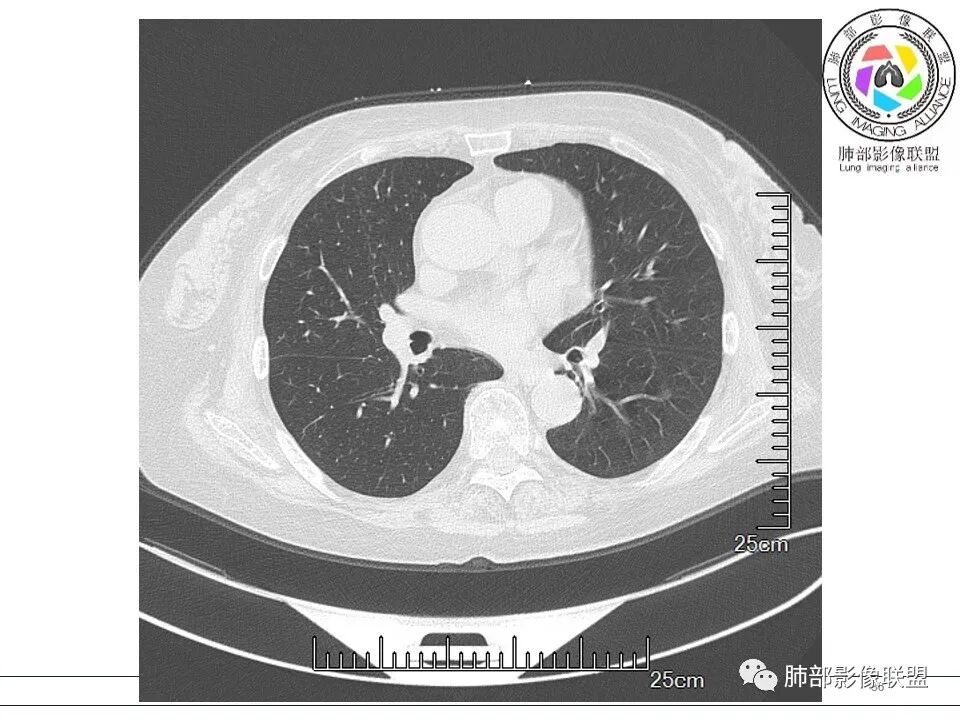

红日初升: 胸膜下结块,平行胸膜,收缩力较强,肉芽肿样边缘,考虑炎性,小卫星灶、似有凝固性坏死,隐球>op

小兜: 晨读,女,70岁,风湿性多肌痛病史一年,半月前体检发现肺部阴影,无症状,口服药物治疗。现片示:右肺胸膜下条形实变影,局部层面似见多结节融合,周边伴条索影。下方近叶间胸膜处斑片状实变影伴条索影,宽基底与胸膜相连。综合考虑为炎性病变,隐球菌或OP可能

宇宙: 右肺上叶胸膜下结节,多结节融合,长轴平行胸膜,边缘模糊,周围长索条,胸膜牵拉,近端支气管充气扩张,考虑隐球菌,鉴别OP

玫: 晨读:右肺上叶胸膜下软组织密度影,边缘模糊,周围见条索影及少许磨玻璃影,轻度胸膜牵拉,考虑炎性病变。

衡妈: 老年女性,右肺上叶沿胸膜下不规则实性病灶,长轴平行于胸膜,有结节融合感,边缘部分彭隆部分平直,周围可见数条纤维灶影,病灶内可见充气支气管征未达远端,首诊考虑慢性炎性肉芽肿,隐球菌?机化性肺炎?建议增强扫描及ct下穿刺活检。

晨读:女,70,未诉症状。风湿性多肌痛病史,口服强的松等药物治疗。胸部CT:右肺上叶多发不规则斑片影,沿支气管分布,部分病灶侧向融合、平行于胸膜,边缘平直内收为主、部分彭隆,周围模糊晕、可见数条纤维灶影,胸膜牵拉,病灶内可见充气支气管征、管腔不畅,考虑慢性炎症,PC?OP?鉴别腺Ca、SCLC等。

良孑: 右肺胸膜下多发结节,长轴与胸膜平行,部分病灶有多结节融合,可见近端支气管充气征,有晕征及晕中软毛刺,长期口服激素病史,抗炎效果欠佳。病灶形态单一,无播散性树芽,结节内无支气管穿行,单侧发病,收缩力差,可排除TB,OP及淋巴瘤,综和考虑支持隐球菌

5、分布:隐球菌肺炎是肺泡性炎症,病灶分布多位于胸膜下,可紧贴胸膜,也可与胸膜邻近,病灶长轴与胸膜平行。(划重点,分布特点非常重要,因为隐球菌如果没有荚膜,会被巨噬细胞吞噬,在人体内是无法生存。隐球菌孢子吸入后,要有高浓度的CO2的条件下,才能形成荚膜,所以肺泡内、胸膜下多见)

10、“葫芦兄弟”:邻近胸膜多发结节,形态接近,排列呈长串状。